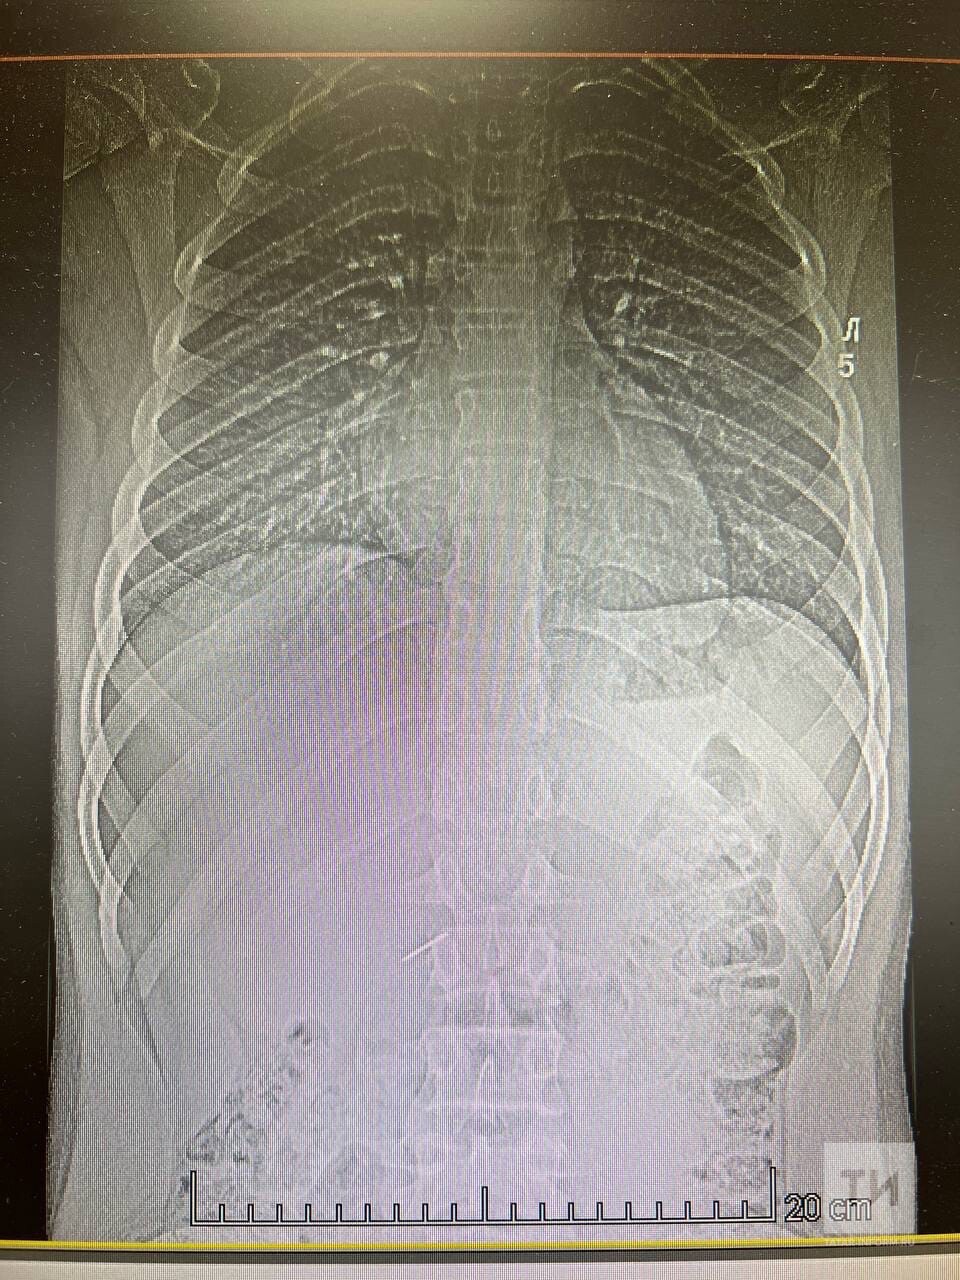

Во втором случае подросток проглотил иголку от циркуля. В этот раз также обошлось без страшных последствий и врачам удалось извлечь иглу из желудка мальчика. В обоих случаях операции проводились эндоскопическим методом под наркозом.

Фото: © пресс-служба КДМЦ